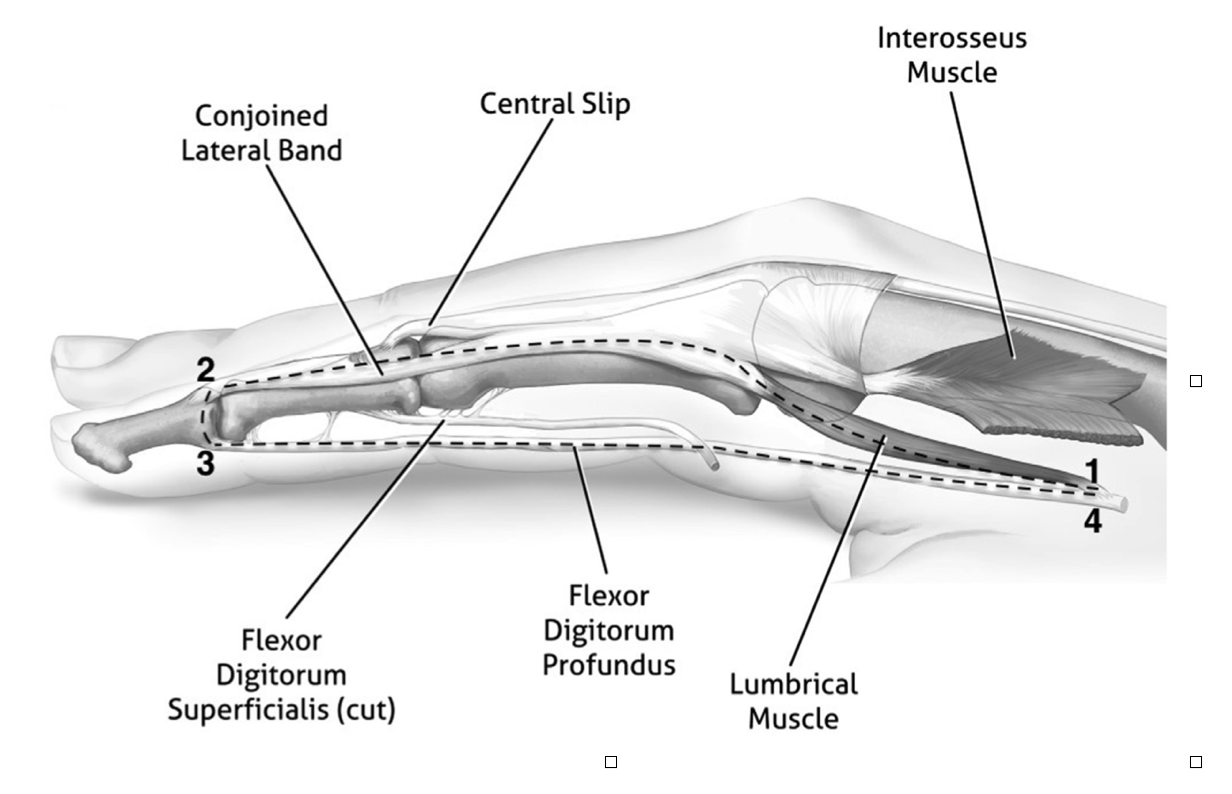

Rapid Review: Is Finger Splinting Necessary after Flexor Tendon Repair?

Outcome of Flexor Tendon Repair Using Eight-Strand Core Stitch Without Postoperative Finger Splinting Reference: El-Gammal, T. A., Kotb, M. M., Ragheb, Y. F., El-Gammal, Y. ...